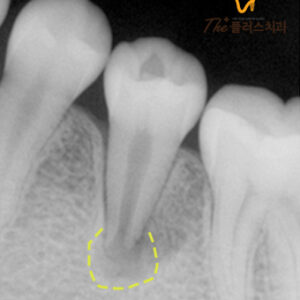

22. 울산남구치과 브릿지에 구멍이 났어요.

울산남구치과 브릿지에 구멍이 났어요.   안녕하세요. 모든 진료에 진심을 다하는 곳, 더플러스치과입니다.   치아를 잃게 되었을 때 이를 대체할 수 있는 방법으로는 임플란트나 브릿지, 틀니 등 다양한 방법이 있습니다.   그중에서도 브릿지는 상실된 치아의 인접한 치아를 삭제한 후 지대치로 사용하여 더보기…